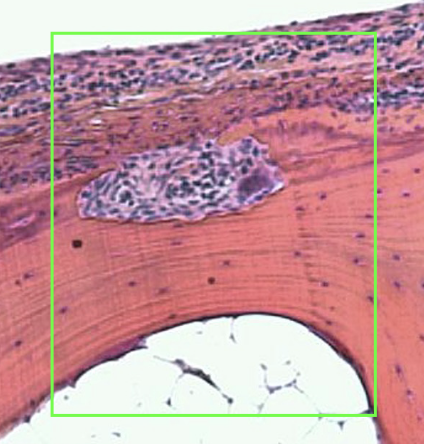

what does this histological image show

osteoclasts in resorption cavity